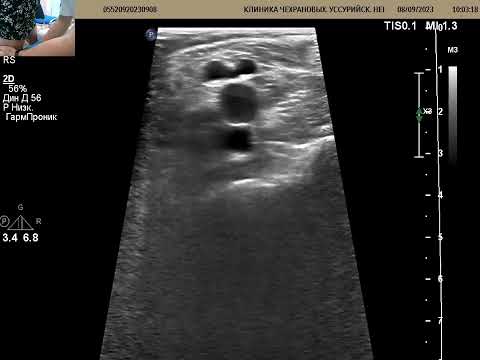

УЗИ вен ног. Есть ли тромб? Почему есть отек?

Тромбоз глубоких вен. УЗИ вен нижних конечностей.